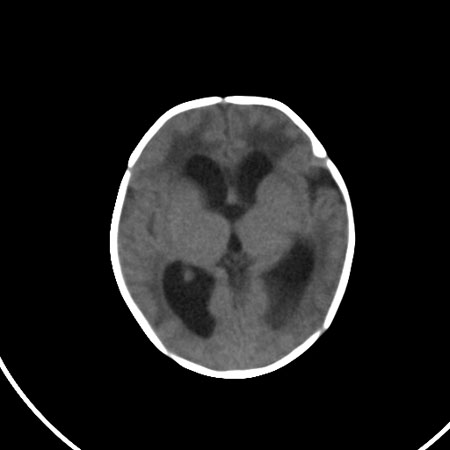

以下是引用小初学者在2009-1-10 17:51:00的发言:[br]考虑缺血缺氧性脑病后遗性改变。

以下是引用拾荒者在2009-1-10 19:23:00的发言:[br]生后有蛛网膜下腔出血病史,现幕上脑室明显扩张,脑室周围白质局限性密度减低,考虑hie脑病后遗表现。